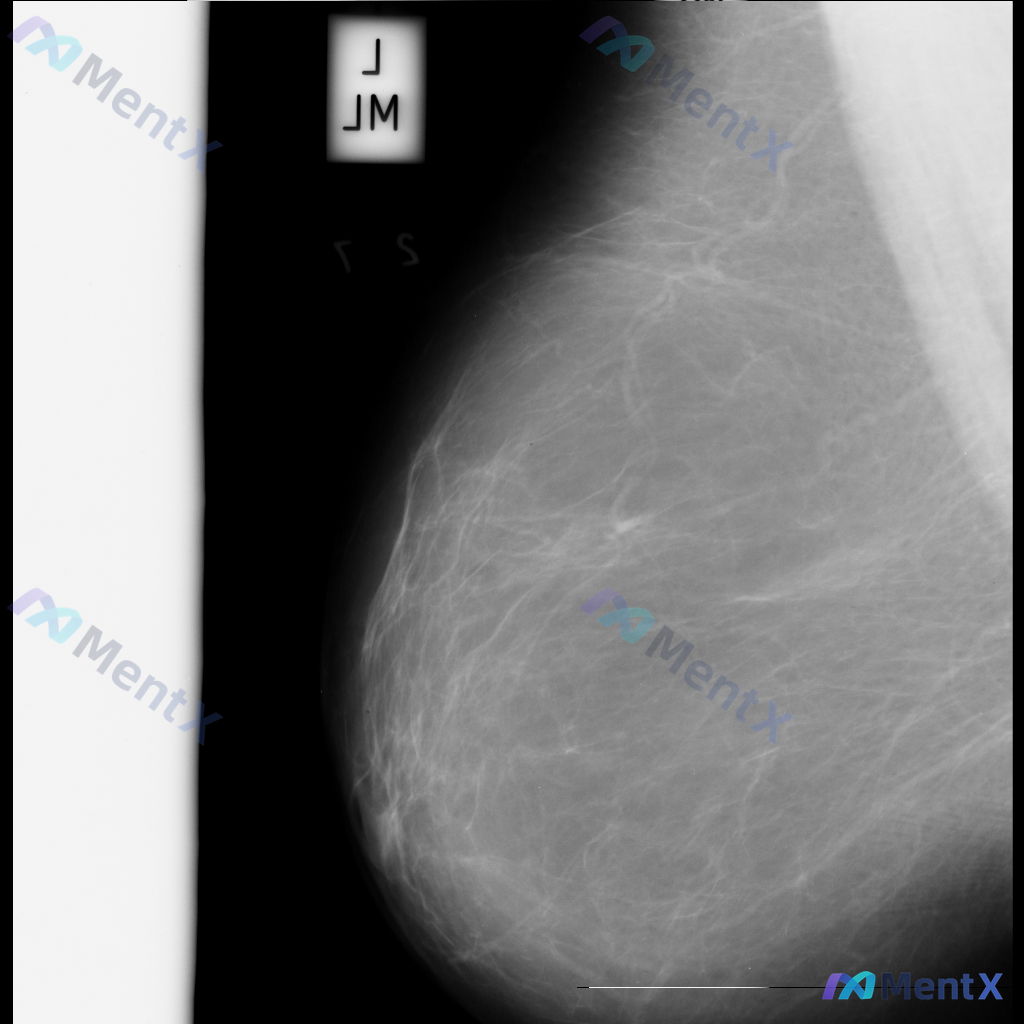

整理到一张乳腺钼靶影像的读片资料,分享给大家讨论。 影像表现:左乳中上象限可见一不规则形高密度致密影,边界部分模糊;内部可见细小、簇状分布的钙化影;同时局部乳腺腺体结构有轻度扭曲和牵拉。 目前需要判断的是,这组表现更支持哪一类情况?

整理到一张乳腺钼靶影像资料,影像所见:左乳中上象限可见不规则高密度致密影,边界部分模糊或伴毛刺状改变,局部乳腺组织结构可见轻度扭曲。 想和大家讨论一下:单看这张影像的异常表现,你认为用哪个术语描述最贴切?